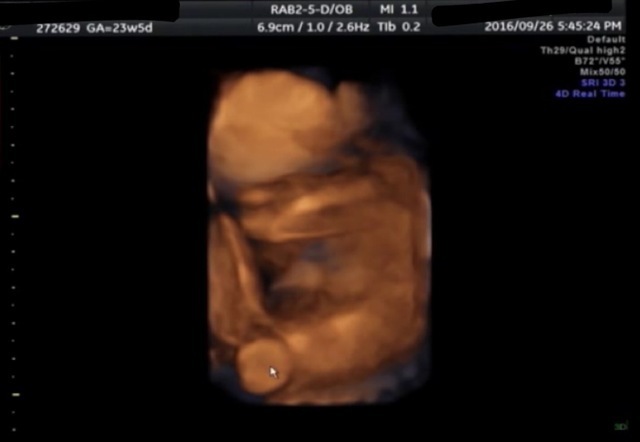

23週5日(23w5d・男の子)|AIS さん(24歳)

いつも検診の時に顔もせてくれるかなーっと楽しみにしていてもなかなか見せてくれず、あ!赤ちゃんの顔だ!と思ったら、後ろを向き、腕に顔を置いていて、まるで大人が机に顔を伏せて昼寝をしているかのようなポーズ! かわいくて笑ってしまいました。